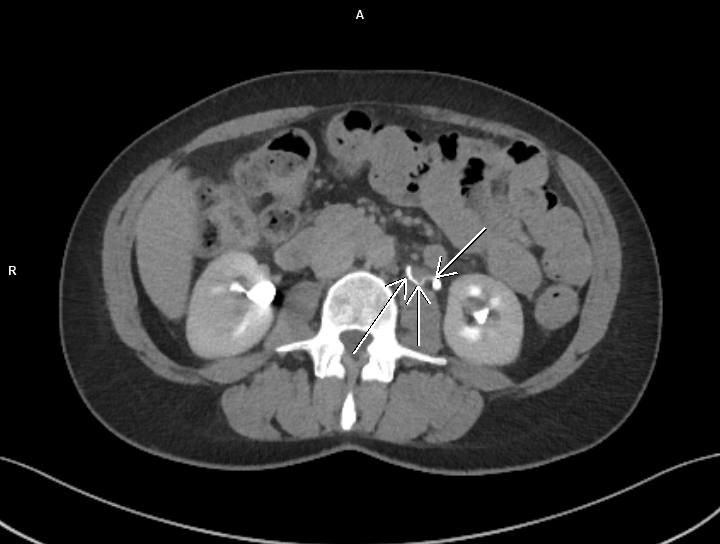

Figura 1: reconstrucție axială din achiziție CT abdomino-pelvină postcontrast tardiv

Discuţie caz nr 105: Diagnosticul diferențial al uretero-hidronefrozei include și compresia extrinsecă a ureterului de către vena ovariană stângă / vena cavă inferioară; pe examinarea tardivă postcontrast se evidențiază decalibrarea ureterului la trecerea posterior de vena ovariană stângă – datorită faptului că structurile venoase sunt ușor compresibile, această cauza secundară de uretero-hidronefroză este rară.